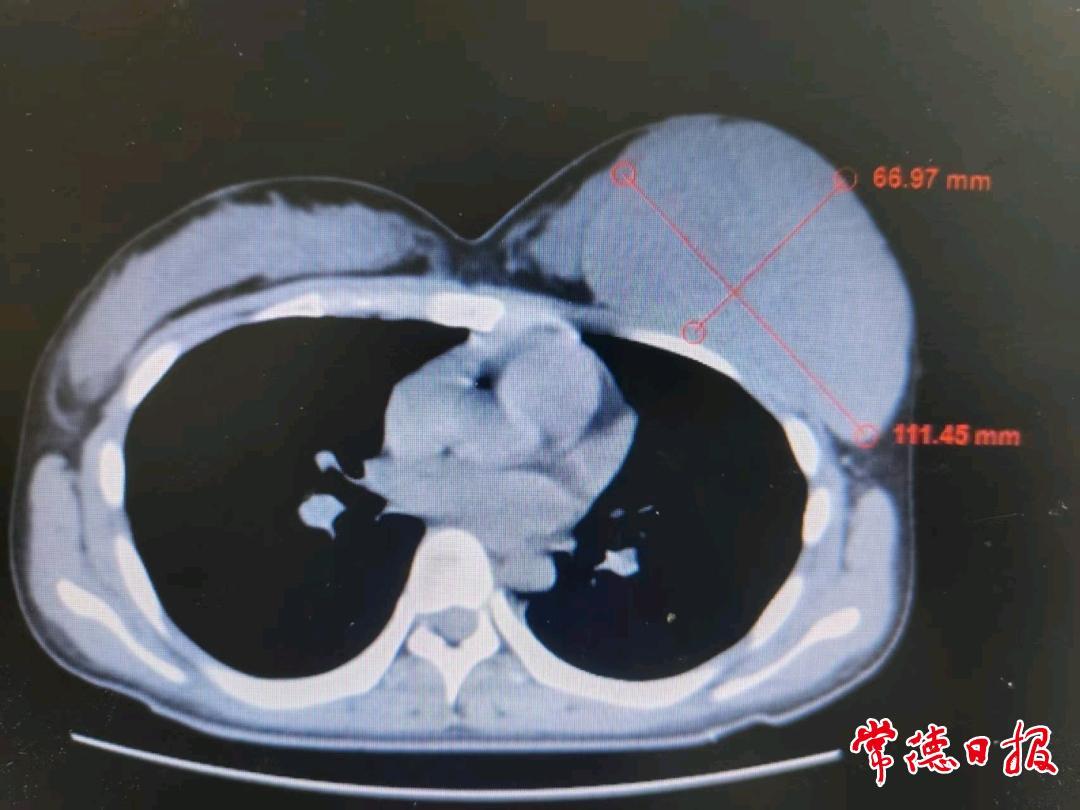

意识到问题的严重性后,家长立即带小美就医检查,彩超结果令人震惊:左侧乳房内竟长着一个巨大的肿瘤。随后,小美来到常德市第二人民医院寻求治疗,经详细检查和穿刺活检,最终确诊为幼年性乳腺纤维瘤,属于良性病变。尽管是良性,但其体积巨大(术前影像显示如柚子大小),必须尽快手术切除。经过周密的术前准备,医师团队为小美成功实施了肿瘤切除手术。手术过程顺利,术后小美恢复良好。